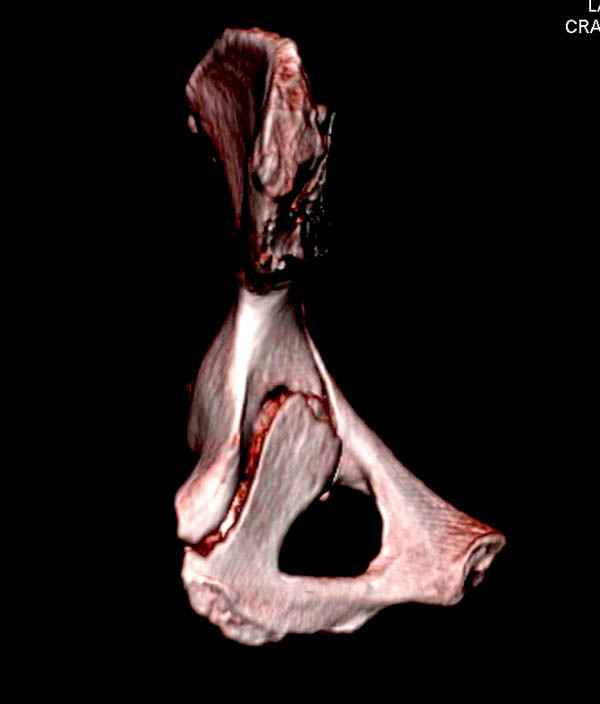

Уважаемые коллеги! С прошедшеми Вас праздниками. Теперь ближе к трудовым будням. Поступила 16 летняя девушка неделю назад. Механизм травмы падение с 5 этажа. Краткий диагноз:закрытый перелом левой ключицы, левого плеча, закрытый вертикально и ротационно нестабильный перелом костей таза:закрытый перелом левой подвздошной кости, переломы лонной кости справа, перелом обоих колонн вертлужной впадины слева;субкапитальный перелом шейки левой бедренной кости со смещением. По тактике лечения таза возникли следующие вопросы: 1. С чего начать - фиксации переломов вертлужной впадины или устранения деформаций таза? 2. Надо ли фиксировать шейку или фиксировать бедро в аппарате вместе с тазом, а после сращения таза планировать ТЭП ТБС? Если имеются еще какие подводные камни, будем рады выслушать.Спасибо.

На снимке ацетабулума редко встречающийся очень низкий перелом, наверное, трудно было репозицию через один доступ? Перелом как бы замкнулся в квадрилатеральной поврехности.